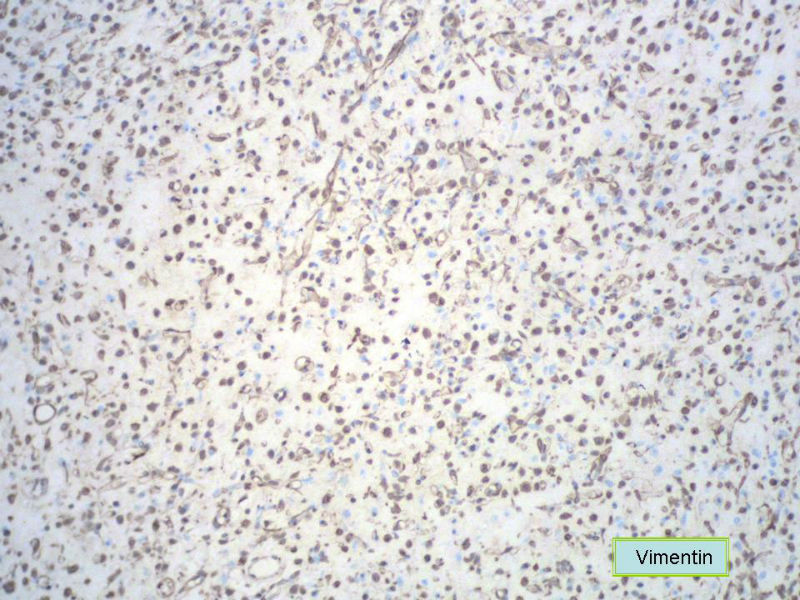

男,27岁,右股骨上段皮下肿物1年余,无明显疼痛,检查肿物明显隆起于皮下,边界清楚,手术完整切除肿物。肉眼,肿物6X6X5厘米,外观多结节状,似有包膜,切面灰白色,质韧。

特别提示:镜下核分裂3-4/HP.

3. 本例组织学改变与粘液性脂肪肉瘤,粘液样纤维肉瘤,纤维粘液样肉瘤,骨外粘液样软骨肉瘤都有重叠之处,且镜下并未见典型结构。由此,免疫组化结果就尤显重要。特别是专业书籍提到,突触素或嗜铬素阳性,对鉴别诊断有重要意义。我用CGA,也是在以上几个肿瘤中举棋不定而为。NSE和CK没用,其实我想用更多的抗体来证实更多的东西,但患者的经济条件不太好,遗憾!